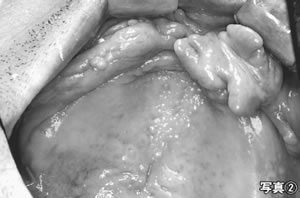

六〇代の男性。上下無歯顎。上顎義歯が不安定で外れやすく、咀嚼障害がありました。上顎歯肉部には、これまでの不適合義歯により「ビラビラした歯ぐき (繊維腫)(写真2)」ができていました。この浮動性の歯肉が、義歯の安定性と顎堤(がくてい)への吸着力を阻害した原因でした。NSTでそのことを報告 し、歯科受診をすすめました。